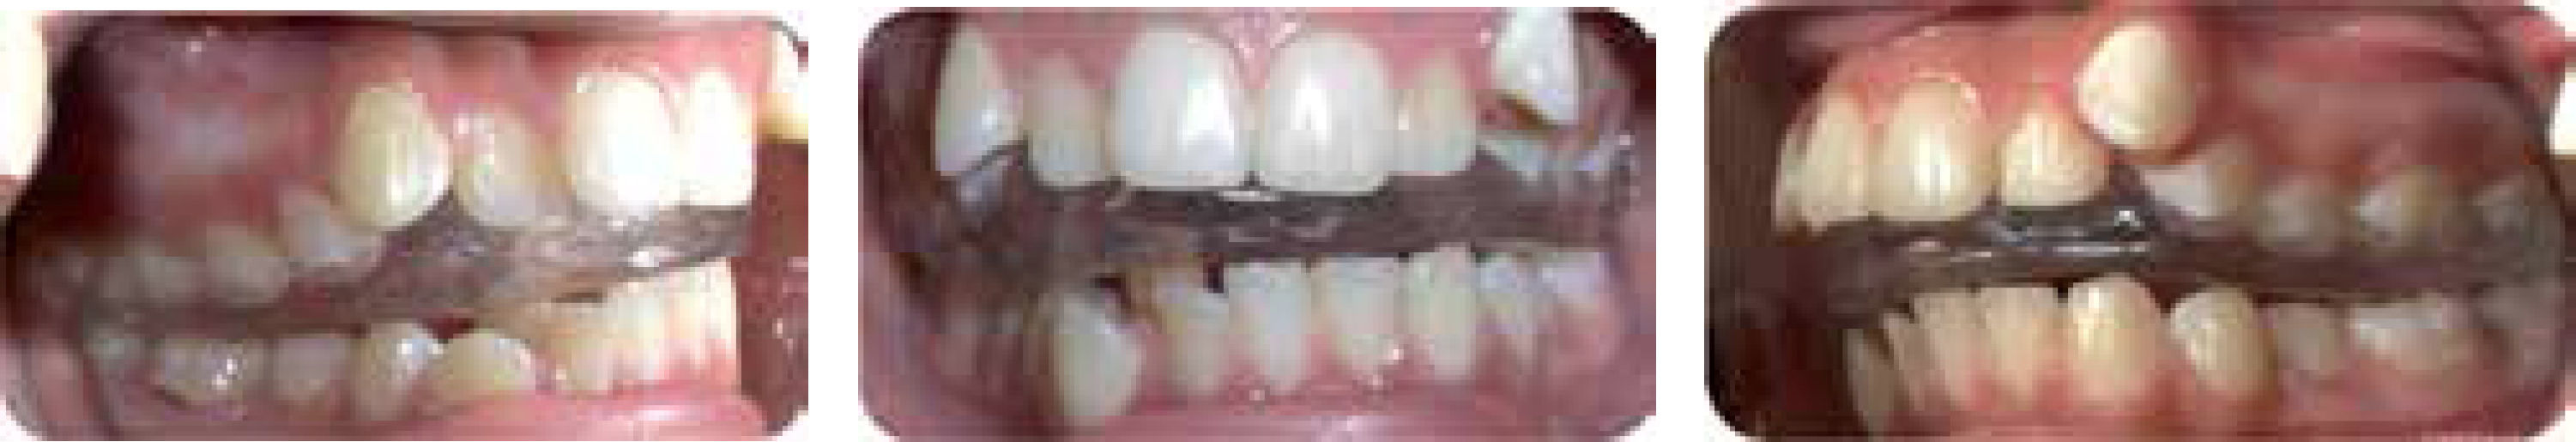

REPORTE DEL CASOPaciente femenino de 13 años de edad, que presenta sintomatología dolorosa muy fuerte e hipertonicidad muscular generalizada, vértigo, imposibilidad para caminar, limitación de movimientos mandibulares, masticación débil y apertura bucal máxima de 17mm (Figuras 1 y 2). Canalizada de neurología, se presenta a la clínica para no tener dolor. Cefalométricamente presenta clase II esqueletal por retrognatismo mandibular, micrognatismo, tendencia al crecimiento horizontal, biproclinación y biprotrusión dentoalveolar. Al análisis facial muestra perfil convexo y biproquelia. Particularmente padece dolor de ATM bilateral, así como dolor muscular generalizado. Funcionalmente realiza movimientos de apertura y cierre anormales y limitados, contractura muscular generalizada, hábito de proyección lingual, succión de labio y masticación débil. Dentalmente presenta clase canina derecha e izquierda no valorable, apiñamiento severo anterior superior e inferior, sobremordida vertical aumentada, sobremordida horizontal aumentada, desviación de líneas medias, arcada superior e inferior no ideales (Figuras 3 y 4).

Primeramente se prescribió Robaxisal®, 1 cada 8 horas por 15 días, aunado a fomentos de agua caliente y masajes en los músculos de la cara y cuello tres veces al día como terapia paliativa. Se colocó férula de miorrelajación superior (Figura 5), se cita a la paciente cada 15 días para revisión de puntos de contacto y desgaste en la férula, los cuales alisábamos, el aparato fue usado por tres meses, tiempo necesario para determinar si el problema que presentaba era causado por la maloclusión. Al mejorar la apertura, masticación y disminución del dolor se confirmó que el tratamiento sería ortodóntico y no se estaba originando por un problema sistémico como reumatismo juvenil; así iniciamos el tratamiento.